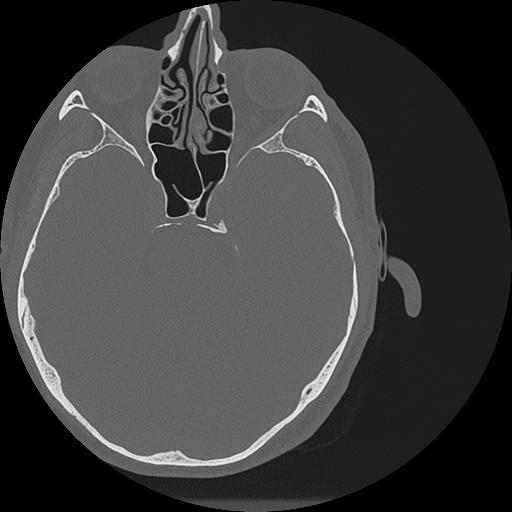

7 HUESO,,Vol,0.5,HUESO,,